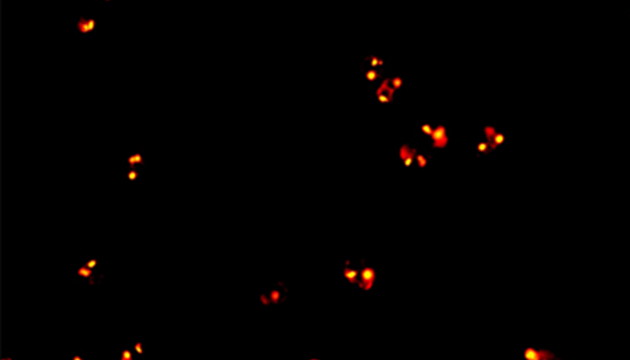

CTC检测用于上皮肿瘤,如胃肠癌、皮肤癌等。检测分四步:富集、CD45染白细胞、CK染CTC、DAPI染核。有DAPI、CK荧光且无CD45荧光,大核细胞为CTC;有DAPI、CD45荧光为白细胞。

CTC检测面临仪器通用性差、多色荧光阅片繁琐及高灵敏度成像难三大难点。新技术如微流控芯片有望取代专用仪器,提升富集效率。使用电动荧光显微镜搭配微流控,可更高效率进行CTC成像和阅片。另外为满足高灵敏度成像需求,建议配置优质LED光源、高效滤光片、半复消色差或以上物镜及高灵敏度相机。